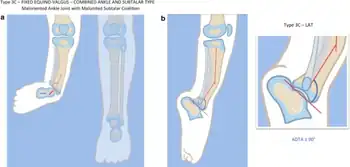

![]() | |

| a, b) Paley type 3c fibular hemimelia | |

- Absence of the lateral part of the ankle joint (due to absence of the distal end of the fibula), and what is left is unstable; the foot has an equinovalgus deformity